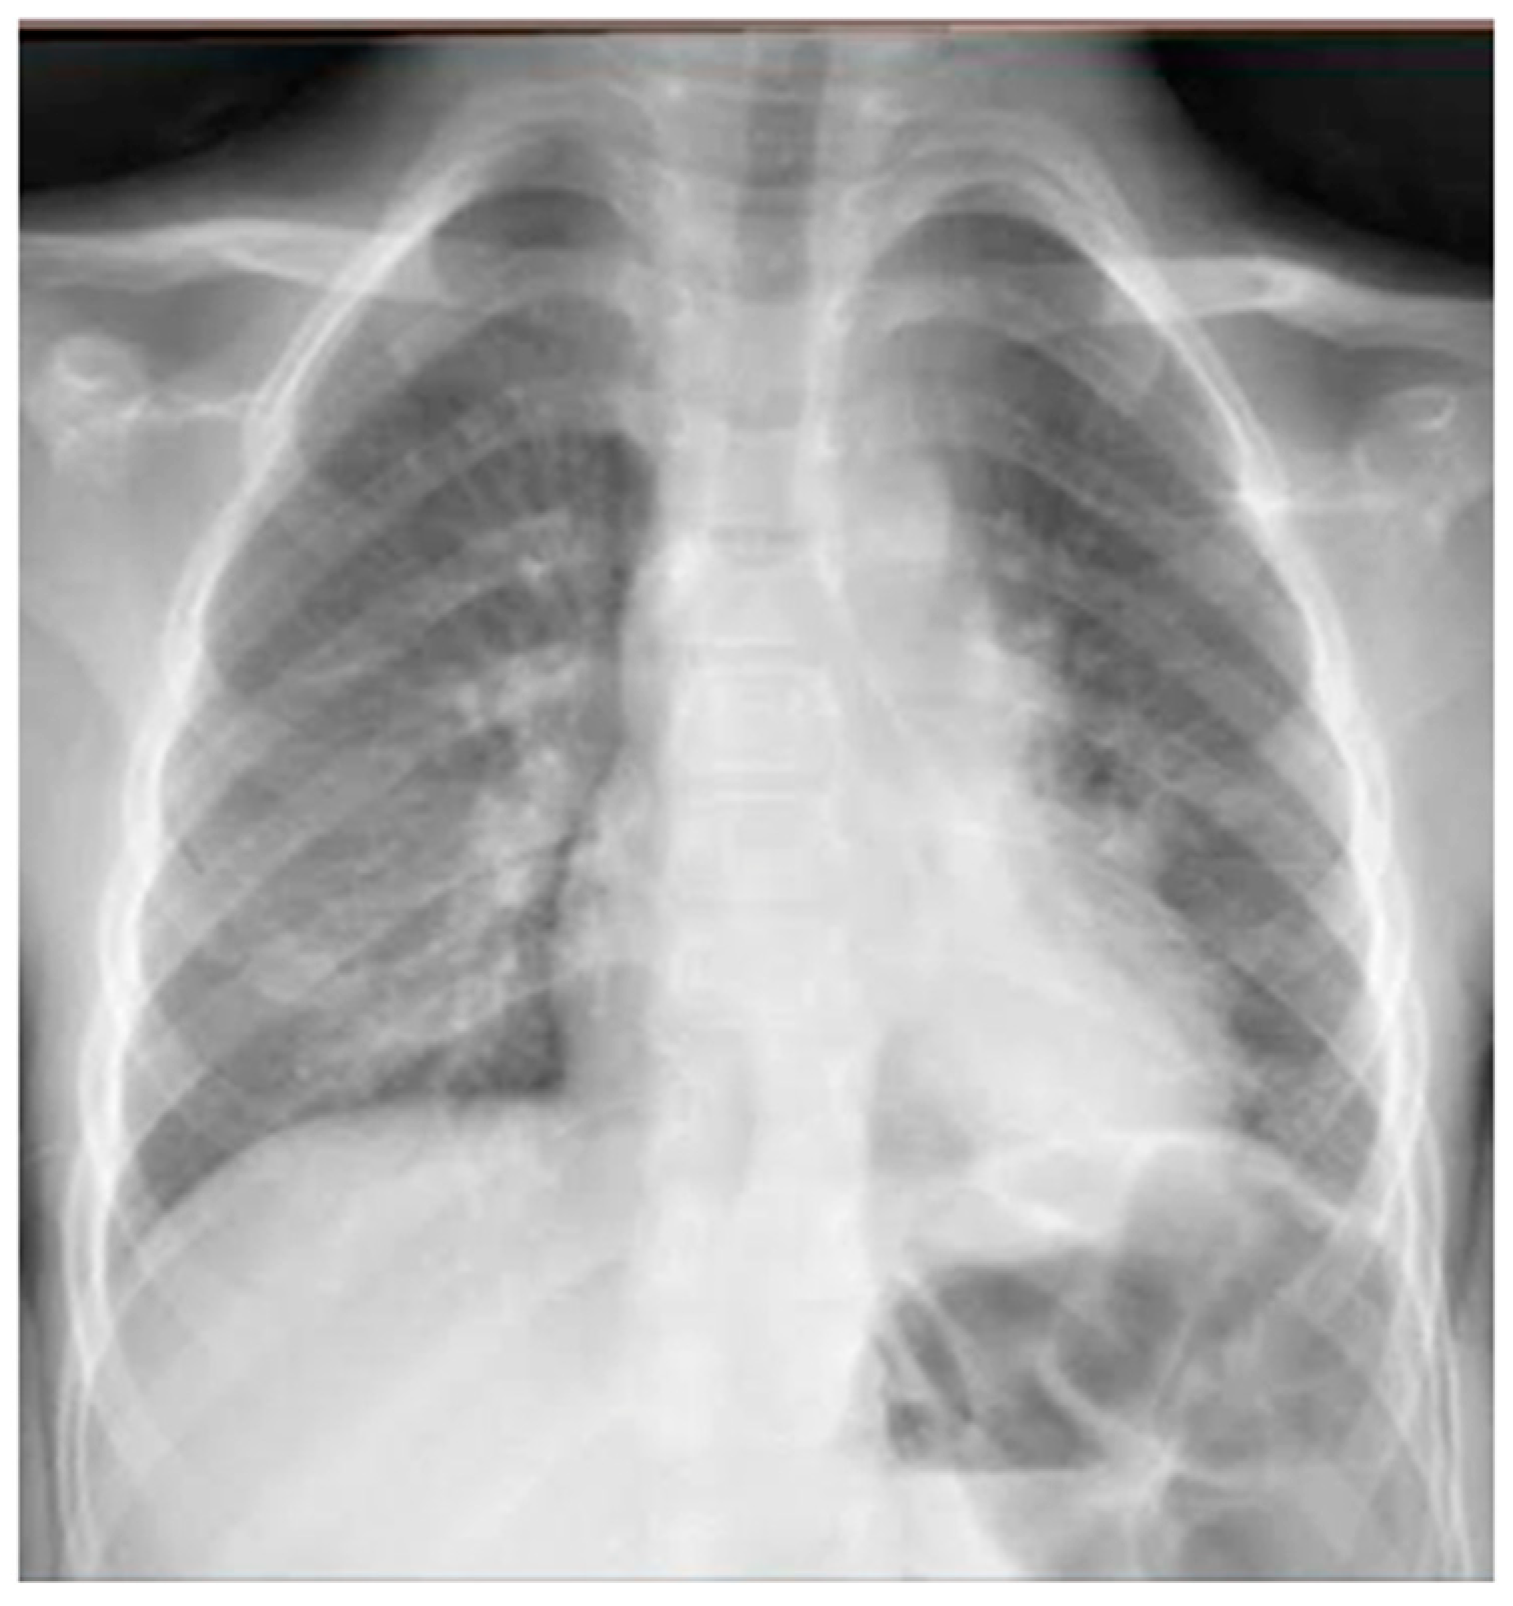

He came to our attention at the PED for acute onset of severe respiratory distress with diffuse bronchospasms and moderate-to-severe acute asthmatic attack: he presented severely dyspneic and tachypneic, unable to speak, he was tachycardic, and he had an oxygen saturation of 88–90% with consequent oxygen requirement. A chest X-ray was performed in the pediatric emergency room to rule out respiratory complications in consideration of the severity of the severe clinical picture. The radiographic picture (Figure 2) was interpreted as an inflammatory type consolidation. However, the child was apyretic, and the inflammation indices were negative, as were the molecular and culture microbiological tests of the airways for both viruses and bacteria.

Figure 2.

Chest radiography shows, on the left inferior lobe, non-specific areas of reduced transparency, associated with obliteration of the left lateral costophrenic sinus. It shows further subtle parenchymal hypodiaphania on the right mid-basal area.

In any case, therapy for acute asthma attack and antibiotic therapy was set up, and he was admitted to the pediatric ward. Here, at the same time as the clinical evaluation, we performed LUS, which showed the presence of a diffuse SIS, and three areas of lung atelectasis, one of which—present in the left posterolateral basal area—was associated with mild reactive effusion (Figure 3). The LUS picture was highly positive, but excluded the presence of inflammatory/infectious consolidations.

However, regarding chest X-ray, it does not provide useful information for the design of treatment plans for children with acute asthma [16], as in the vast majority of cases, it is completely negative, and in a minority, it is suggestive of atelectasis and/or thickening of the interstitium: elements that are often confused with a radiographic picture of pneumonia, with subsequent administration of antibiotic therapy not necessary to modify the outcome of acute asthmatic attack [16], just as it happened in the first three of our cases. The studies carried out so far are, in fact, all in agreement that chest X-ray is often not helpful in asthma [16].